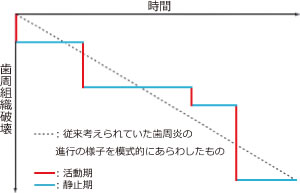

歯周炎の進行

歯周炎の進行は短時間に急速に歯周組織の破壊が進行する活動期と長期間にわたり破壊の進行しない非活動期(静止期)が間歇的に繰り返されます。